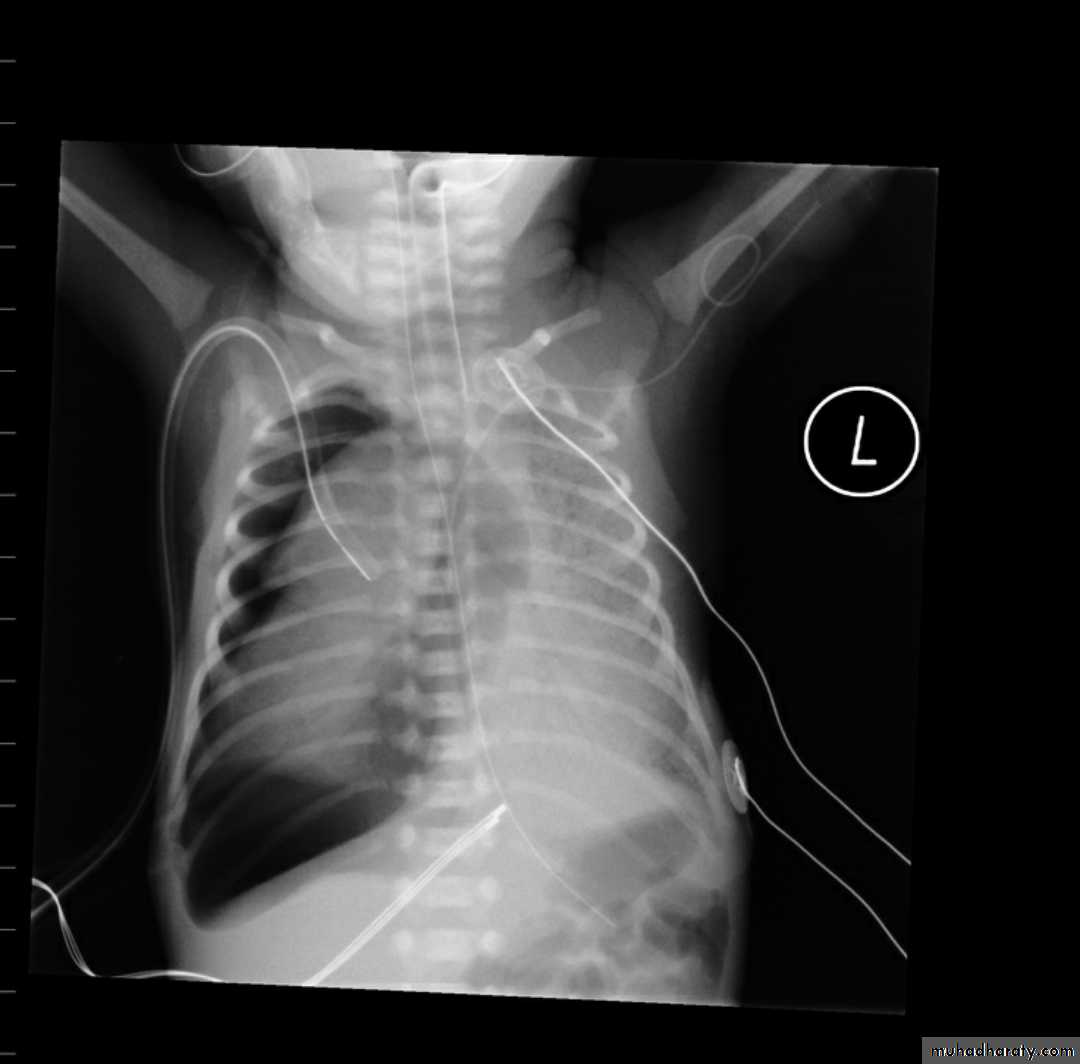

Tension pneumothorax

Radiolucent area devoid of lung markings in the area of the left lung with visible viseral pleural edge.Tension Pneumothorax

Radiolucent area devoid of lung markings in the area of the right lung with visible viseral pleural edge. The mediastinum is pushed to the opposite side